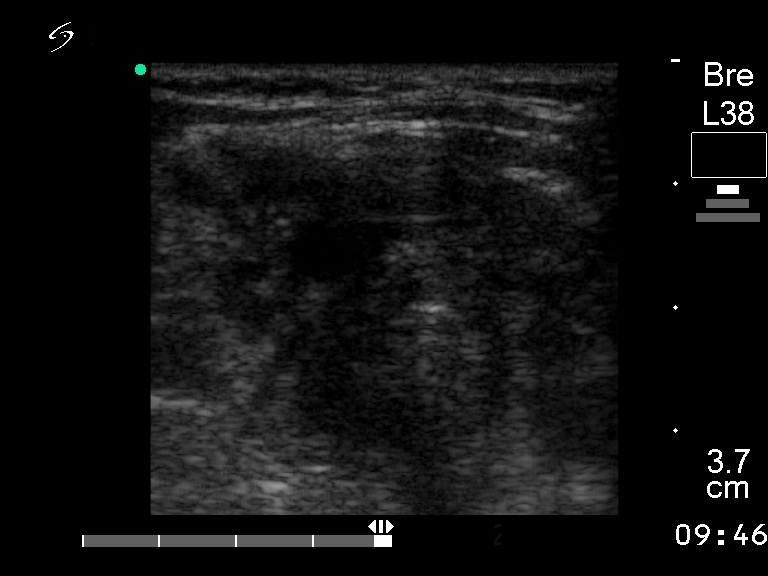

Ultrasonography. There was a large, hypoechogenic inhomogeneous nodule which occupied almost the entire right lobe and the isthmus. The left lobe was intact. There was a hypoechogenic inhomogeneous lesion within the right parotid.